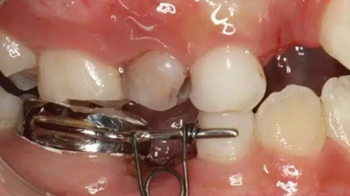

39、推簧加力后合面觀

40、加力后,重新就位合面觀

41、加力就位后測力值200~250克,初級力值偏大,隨著力的衰減力值維持在100~150g左右,直至間隙推開后,力值逐漸遞減為零,作為間隙保持器使用,等待恒牙萌出

42、牙面拋光,試合制作好的間隙恢復器,將曲簧水平部分形成與牙面弧形一致,羧酸鋅水門汀粘結固定

43、粘結后的頰面觀

44、8周后復診間隙推開,自動變換為間隙保持器